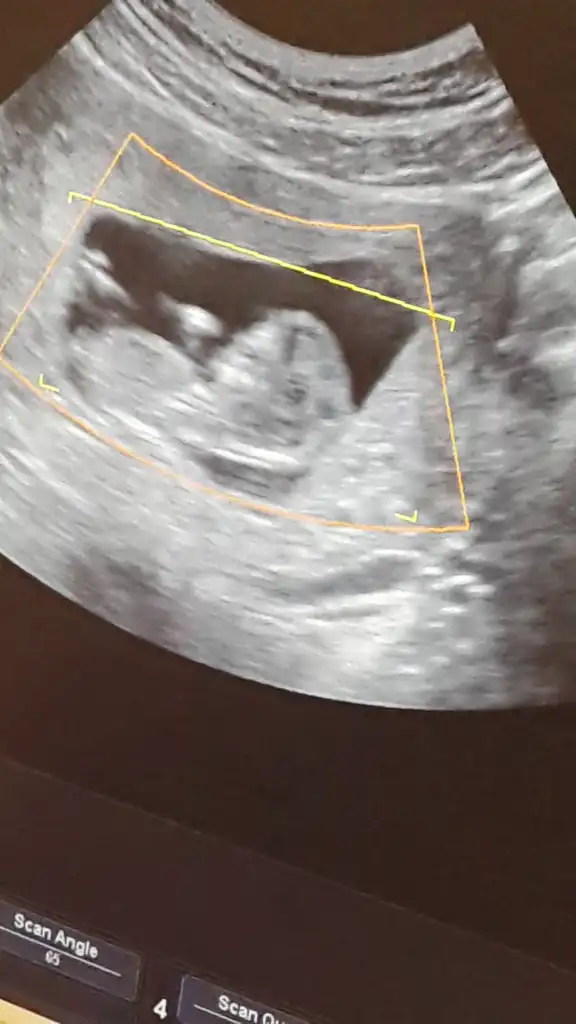

Selamm canlarim bizde 12haftadayiz ilk çocuğumuz çok merak ediyorum cinsiyetini bi annem kız diyo diğerleri erkek anladiklarindan dgl de tahmin yüzüm cok kızardı lekelendi sivilcelendi iştahsızlık var hep pek bisey yiyemiyom ama hayırlısı bakalım sizce kız mi bebisim erkek mi simdiden çok teşekkür ederim hepinize...

• IMG-20150223-WA0001.webp

IMG-20150223-WA0001.webp

17,6 KB · Görüntüleme: 97

kizlar tahminlerinizi merakla bekliyorum